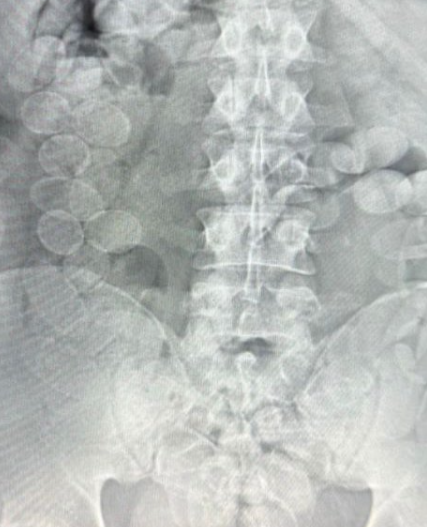

Una vez bajo supervisión médica, se les realizó placa radiográfica donde pudieron visualizar la presencia de las capsulas. Luego, los ciudadanos expulsaron un total de 185 cápsulas.